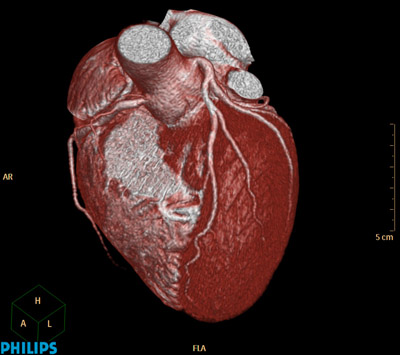

The need for speed continued to push CT machine designers, especially in the medical area. CT scanners for imaging the heart are especially challenging, because of the natural motion of the beating heart. This procedure, known as Cardiovascular Computed Tomography Angiography (CCTA) is a growing application. In this case, the X-ray equipment needs to get around the heart between beats, while the heart is at rest, in order to image the fine blood vessels feeding blood to the heart muscle itself (Figure 2). There are only two options: slow down the heart through sedation or speed up the rotation of the machine.

Philips Healthcare, a major supplier of CT equipment began a new machine design with a fresh sheet of paper in order to find a way to speed up the rotation. According to Philips Healthcare CT Product Manager Robert Popilock, their clinical partners were “interested in performing CT examinations of the heart, requested a system capable of faster rotation speed to improve the likelihood of capturing a “snapshot” (Figure 3) of the vessels supplying blood to the heart wall at the most quiet state.1 ” The solution they found also solved many of the other problems of building precision CT scanning equipment.